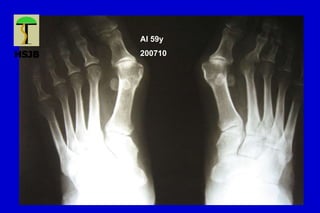

AI 59y

200710

HALLUX VALGUS

Desviación lateral del hallux, con varo del primer MT

Primer grado o leve Ángulo intermetatarsiano < 15ª

Ángulo MTF < 30ª

Articulación MTF congruente

Sublux sesamoidea mínima

Segundo grado o moderado Ángulo intermetatarsiano entre 15 y 18º

Ángulo MTF entre 20 y 40º

Subluxación MTF

Sesamoideo lateral luxado entre 70 y 100%

Tercer grado o severo Ángulo intermetatarsiano >18-20º

Ángulo MTF > 40º

Hallux pronado

Articulación MTF incongruente

Lx sesamoidea lateral del 100%